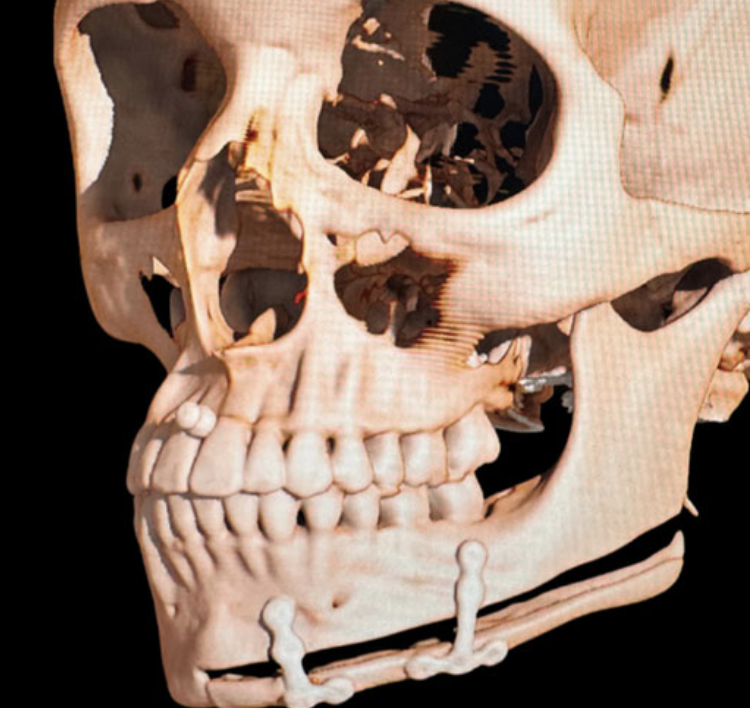

I have a narrow upper jaw so I’m going to see a doctor on the 10th of April to see if I can get a sarpe.

Would a sarpe and then lefort 1 (make my maxilla more prominent) paired with a bimax and genio(fix my lower third) make this morph slightly possible? Ofc I know that it’s impossible to even replicate this morph irl. Just want your thoughts on the direction of procedures that could make it look similar .

I have a narrow upper jaw so I’m going to see a doctor on the 10th of April to see if I can get a sarpe.

Would a sarpe and then lefort 1 (make my maxilla more prominent) paired with a bimax and genio(fix my lower third) make this morph slightly possible? Ofc I know that it’s impossible to even replicate this morph irl. Just want your thoughts on the direction of procedures that could make it look similar .